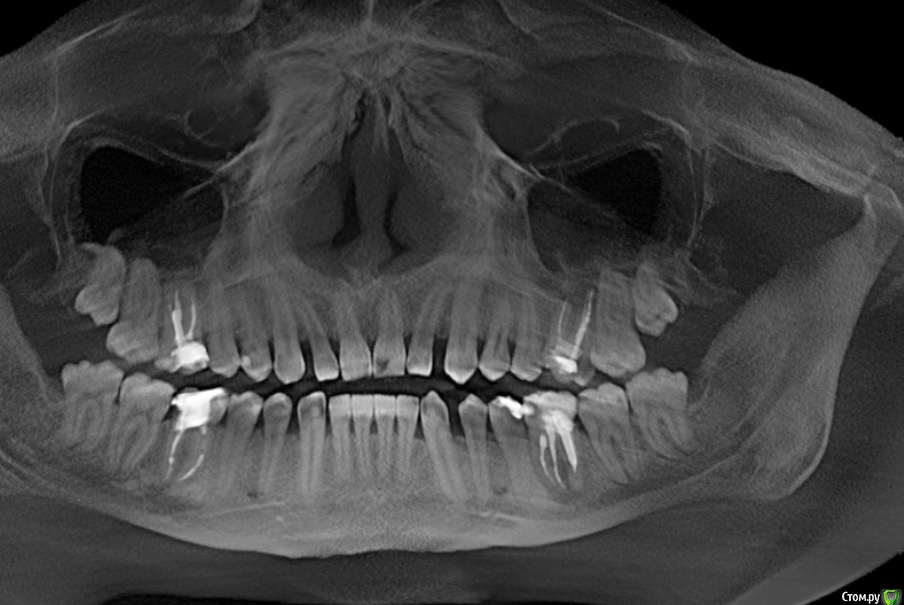

WHITE_ANTONIO Опубликовано 7 декабря, 2015 Автор Поделиться Опубликовано 7 декабря, 2015 Добрый вечер, прикладываю скриншоты КТ Ссылка на комментарий

DmitrySH Опубликовано 7 декабря, 2015 Поделиться Опубликовано 7 декабря, 2015 Прицельный снимки еще будут нужны, в хорошем качестве.26 - ничего особого не видно, просто периодонтит36 - перерасширены каналы, возможно наличие трещины или перфорации.16,46 - тоже требуют лечения Ссылка на комментарий

DmitrySH Опубликовано 7 декабря, 2015 Поделиться Опубликовано 7 декабря, 2015 (изменено) на основании данного снимка судьба зуба 36 под вопросом,а 26 - непонятно, но пока не увидел ничего ужасного. Изменено 7 декабря, 2015 пользователем DmitrySH Ссылка на комментарий

DmitrySH Опубликовано 7 декабря, 2015 Поделиться Опубликовано 7 декабря, 2015 Но я не смотрю на очаги воспаления, меня интересует целостность твердых тканей зуба. Исходя из этого и строится прогноз. На КТ любой материал "фонит" и выглядит больше чем есть. Соответственно есть непонятные моменты. 1 Ссылка на комментарий